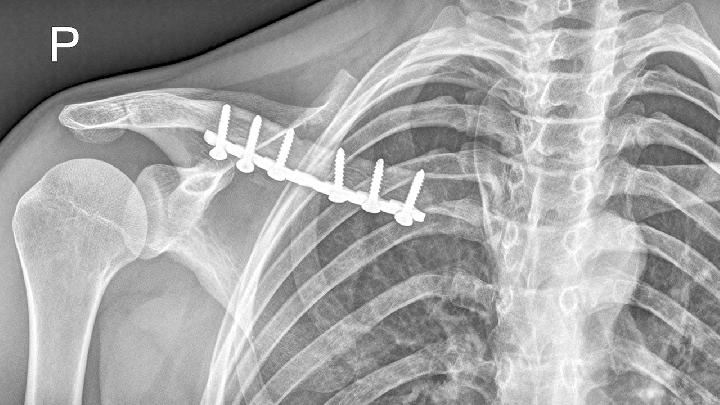

3、外伤:当锁骨部位受到外力的撞击时,可能会使神经和组织受到损伤,从而出现水肿、疼痛。可遵医嘱使用布洛芬缓释胶囊、塞来昔布胶囊、活血止痛胶囊等药物缓解,可有利于促进肿胀和疼痛消退。也可以使用冰袋或者毛巾包裹冰块,对疼痛部位进行冷敷。